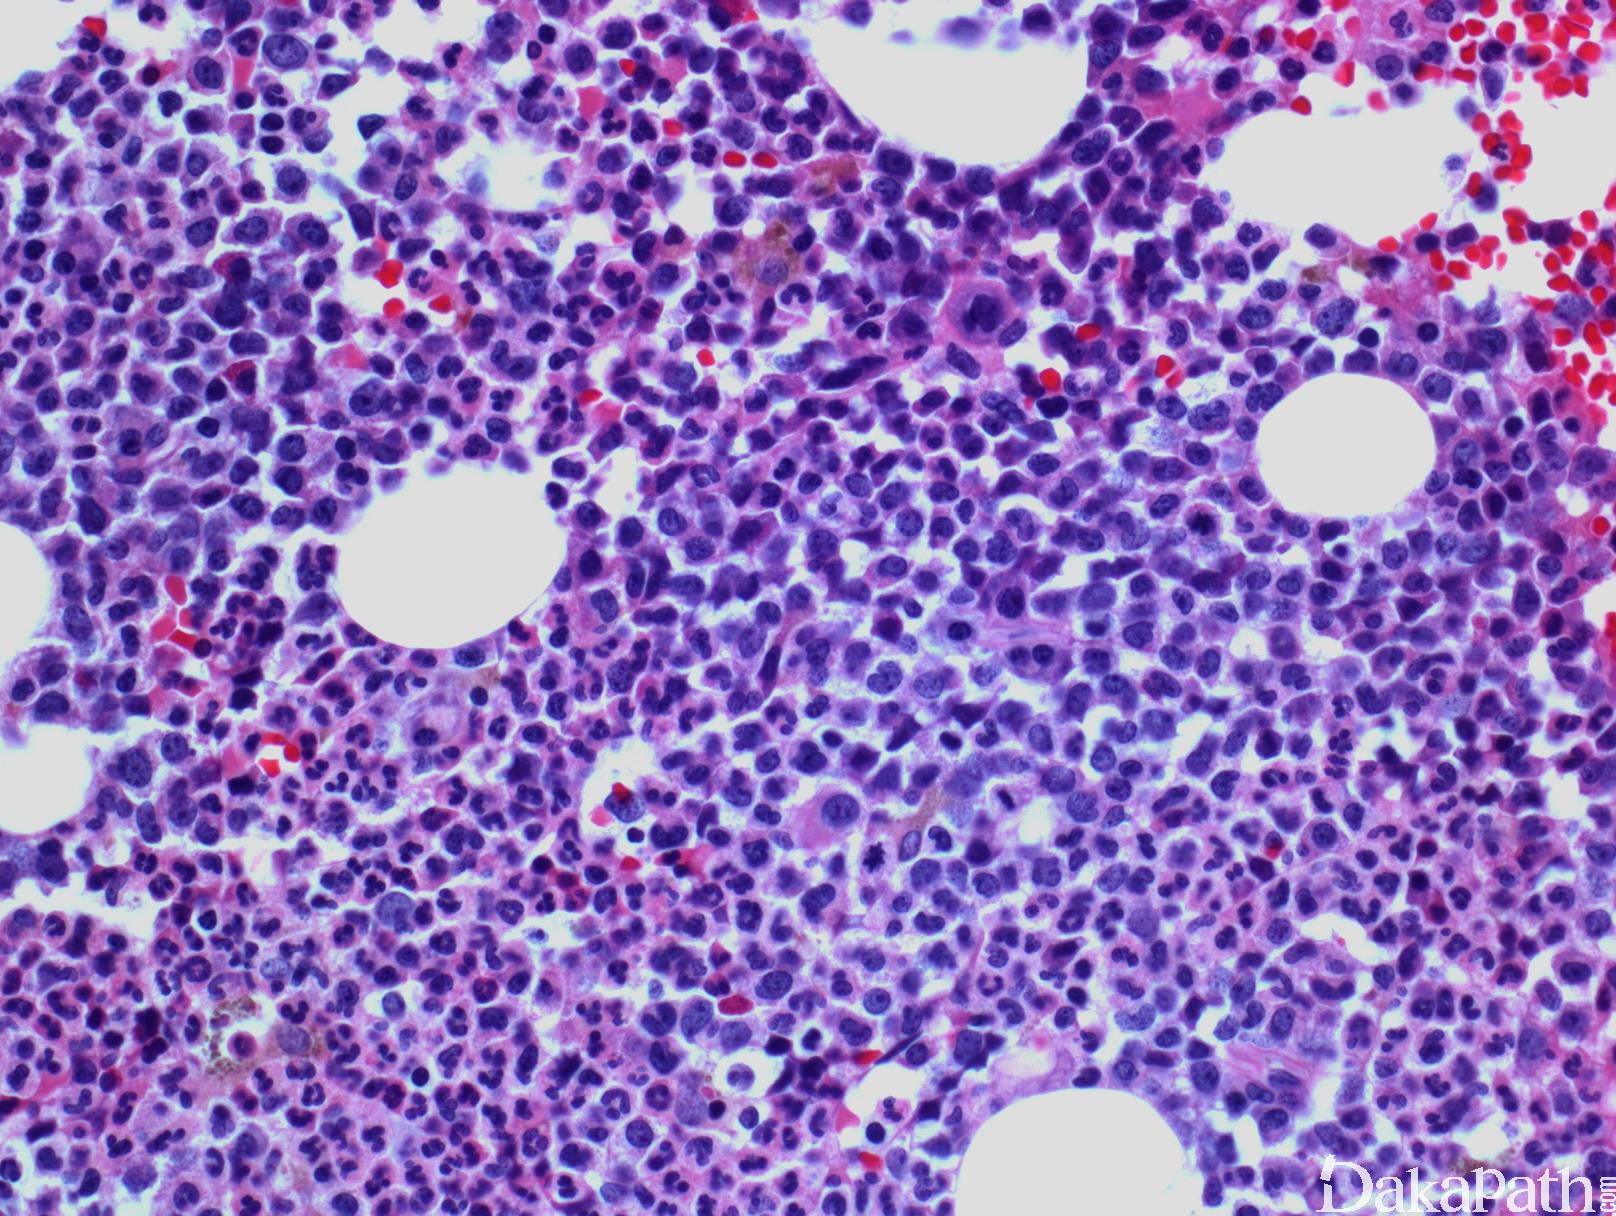

CMML 的标志性特征是外周血单核细胞增高。根据定义,外周血单核细胞计数总是 ≥1×109/L,通常 2-5×109/L,但可以高达 80×109/L,且单核细胞要占白细胞的 10%以上。CMML 外周血中单核细胞为的成熟型,无明显形态学异常;但可出现胞浆颗粒和核分叶异常及纤细的核染色质,具有这类特征细胞最好称为异常单核细胞,用于描述有一定形态学异常和轻微不成熟而又缺乏幼单核细胞特点的单核细胞。幼单核细胞在 CMML 中被认为等同于原始细胞,细胞较不成熟,核染色质细腻、核仁小而不明显,胞质含细颗粒。原始细胞包括原粒细胞和原单核细胞。原单核细胞体积大,胞质丰富,弱噬碱,可含有细颗粒,一个或多个突出核仁。原粒细胞、原单核细胞和幼单核细胞与更为成熟的异常单核细胞和正常单核细胞的区分,对于 CMML 和 AML 的鉴别诊断非常重要。如果原始细胞(原粒细胞、原单核细胞和幼单核细胞)占白细胞总数 20%或以上,则应诊断为 AML。中性粒细胞计数可以增高、正常或减低,前体粒细胞(早幼粒、中幼粒、晚幼粒)应<10%。粒细胞有不同程度的异形性(如少颗粒、低分叶)。可有轻度噬碱细胞增高,噬酸粒细胞一般正常或轻度增多,但偶而显著增高,此时可诊断为 CMML 伴噬酸细胞增高,但髓/淋系肿瘤伴噬酸细胞增高和特异遗传学异常(如 PDGFRB)必须除外。常有轻度贫血,血小板计数不等,可中度减少并形态异常。多数病例骨髓细胞密度增高,但也可以正常,减低罕见。最突出表现是粒系增殖,也总是有单核增生(程度不等),但骨髓涂片形态学不容易辨认。细胞化学或免疫组化染色有助识别单核及其前体细胞。如同外周血,粒系有不同呈度异形性,红系也有轻度异形性,80%病例有巨核细胞异形如微巨核细胞或少分叶巨核细胞。2017 年版 WHO 根据外周血和骨髓中原始细胞(原粒细胞、原单核细胞、幼单核细胞)比例,将 CMML 分为 3 种类型:CMML0,原始细胞外周血中 <2%和骨髓中 <5%,无 Auer 小体;CMML1,原始细胞外周血中 2-4% (< 5%),骨髓中 5-9% (<10%),无 Auer 小体;CMML2,原始细胞外周血中 5-19% (<20%),骨髓中 10-19% (<20%) ,或有 Auer 小体。

免疫表型

流式细胞学白血病细胞表达粒一单核细胞标记,如 CD33 和 CD13;不同程度地表达 CD14. CD68 和 CD64,并可有多个抗原的异常表达,如 CD56. CD2 或低表达 HLA-DR、CD14. CD13. CD36. CD15 或 CD64。一些表型异常,如低表达 CD14,可能反映单核细胞的不成熟。成熟中的中性粒细胞也可出现异常表型特点,如成熟相关抗原表达的不同步。CD34+细胞数增多或出现异常免疫表型的原始细胞群预示可能发生 AML 转化。骨髓活检组织切片免疫组化可与骨髓细胞组织结构联系起来评估细胞成分,溶菌酶与 CAE 细胞化学染色联合应用便于识别单核细胞,单核细胞为溶菌酶阳性、CAE 阴性,而粒细胞二者均阳性。 CD34 组化阳性细胞增高与急性白血病转化相关。